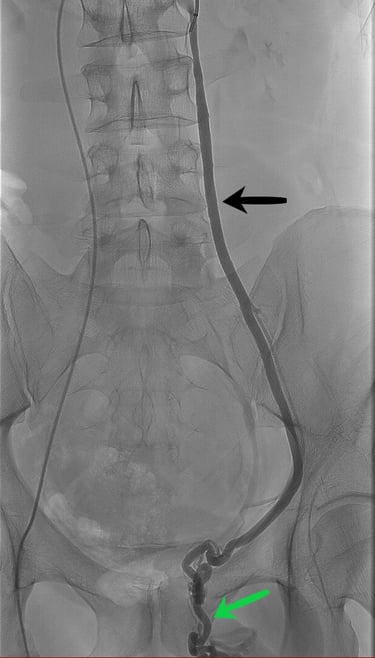

Exemple d'images d'embolisation réalisée dans le service.

Première image, à gauche : phase initiale de diagnostique retrouvant une veine spermatique gauche (flèche noire) dilatée avec reflux du produit jusque dans les veines du testicule (flèche verte).